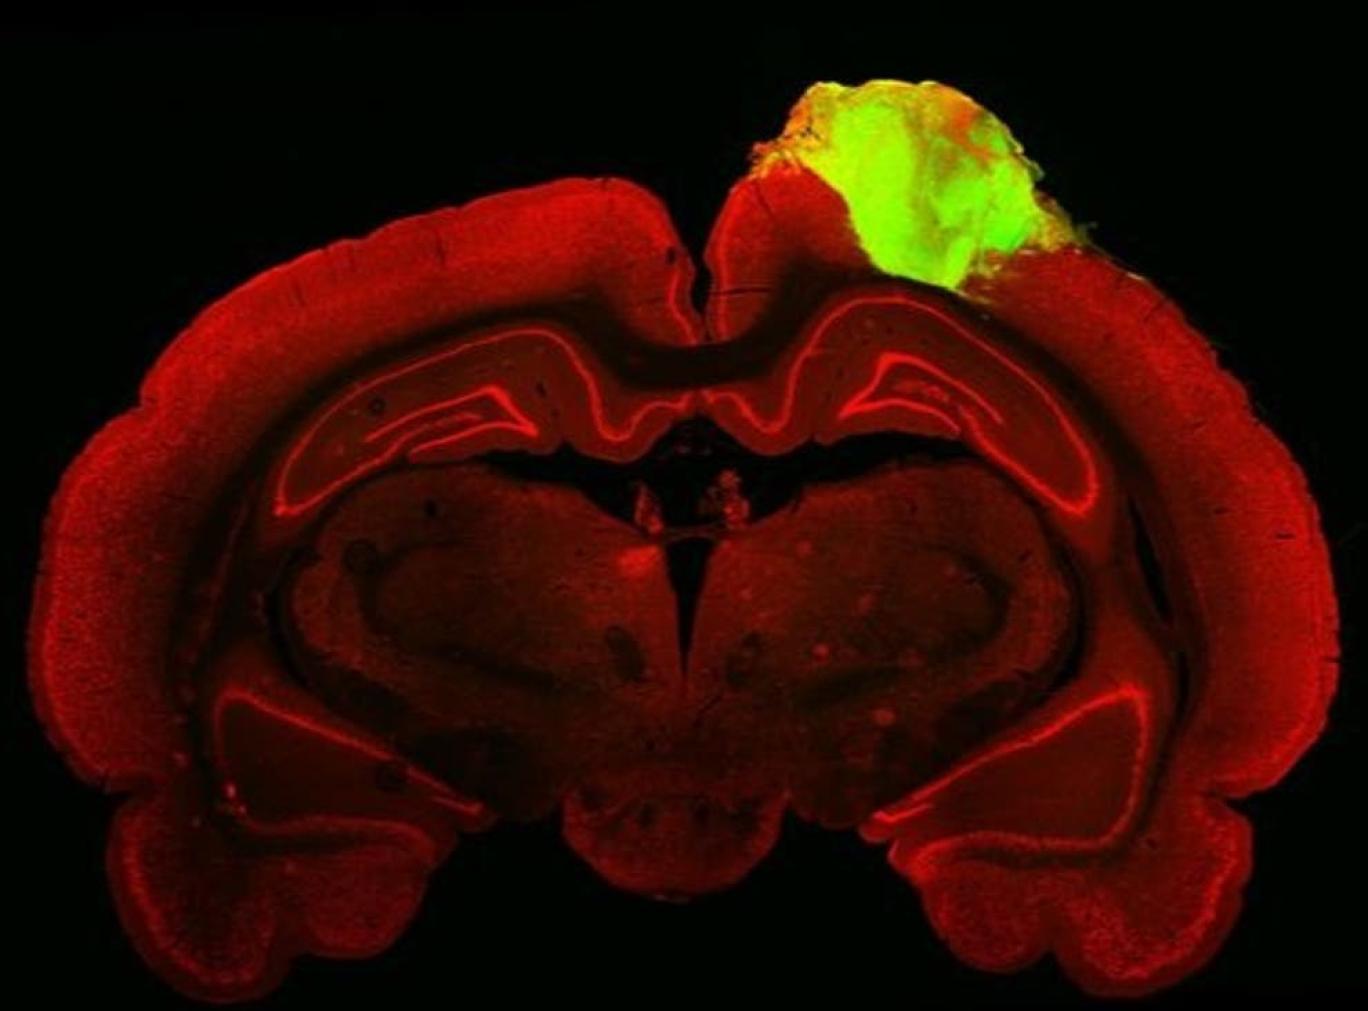

این محققان برای آنکه امتحان کنند این اندامک چگونه با مغز موش یکپارچه شده است، ویروسهای فلورسنتدار به چشم موش تزریق کردند تا ببینند کدام مسیر محل اتصال دو عصب را میپیماید. این مواد فلورسنت مسیر کامل را از شبکیه تا اندامک پیوندی جدید پیمود که نشانگر تحقق یکپارچگی کاربردی کامل بود.

محققان سپس با آزمایش کردن بینایی موش با استفاده از نورهای چشمکزن و عکس متوجه شدند حدود یکچهارم عصبهای پیوندی انسان به این شبیهسازی واکنش نشان دادند.

استادیار چن گفت: «مشاهده کردیم تعداد زیادی از عصبهای درون این اندامک به جهت خاصی از نور واکنش نشان میدهند و این گواه آن بود که این عصبهای اندامکی میتوانستند نهتنها با دستگاه بینایی یکپارچه شوند، بلکه واجد کارکردهای بسیار خاصی از قشر بینایی در مغز نیز بشوند.»

«در اینجا شواهدی ساختاری و کارکردی به دست میدهیم از اینکه پس از پیوند اندامکهای مغز انسان به حفرههای بزرگ آسیبدیده در قشر بینایی در پیشمغز، این اندامکها بهخوبی با دستگاه بینایی موش بالغ یکپارچه میشوند.»